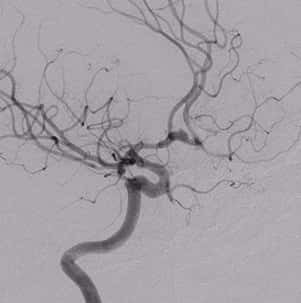

烟雾病是一种以双侧颈内动脉末端及其分支血管进行性狭窄甚至闭塞,同时伴有脑底异常血管网形成的脑血管病。该病于1957 年首先由Takeuchi 与Shimizu提出Suzuki 与Takaku 于1967 将该病命名为Moyamoya 病。烟雾病在国际各地存在明显的地区及种族差异,而其中以亚洲地区黄种人发病率较高。